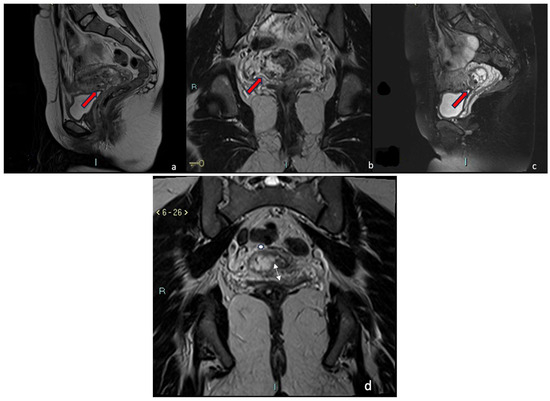

4.1.1. Case 1 (CSP Type I)

4.1.2. Case 2 (CSP Type II)

4.1.3. Case 3 (Low-Implanted Pregnancy)